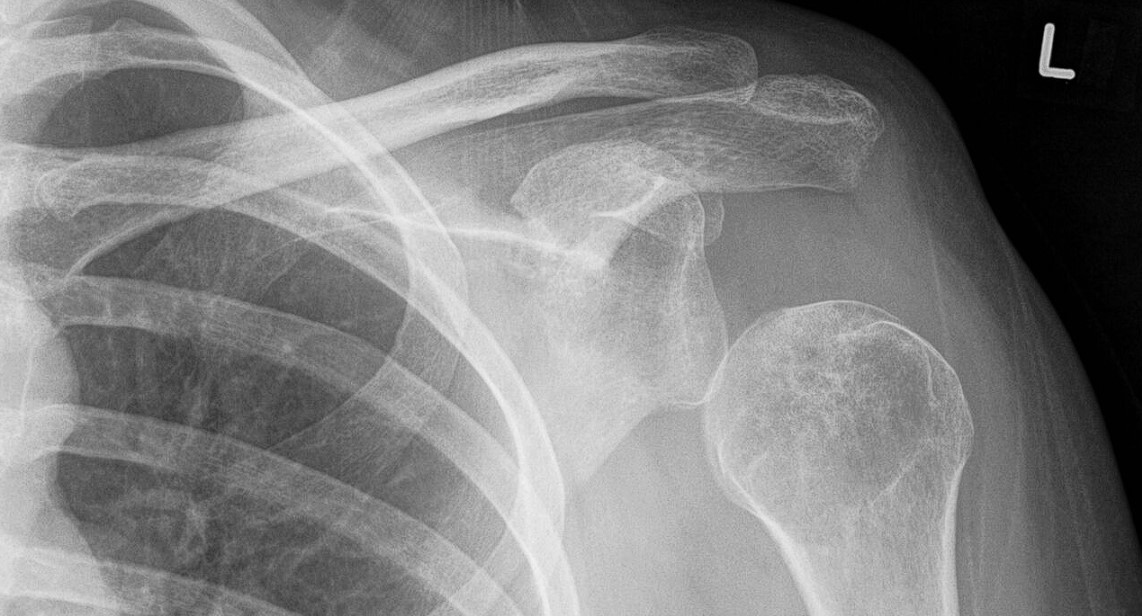

Subluksasyon, eklemlerin tam düzeyde olmayan veya kısmı, yarı çıkığı manasına gelen tıbbi bir terimdir. Eklem yüzeyleri tam olmasa da kısmen temastadır. Tamamen ayrılması ise dislokasyon olarak adlandırılmaktadır. Ciddi yapısal yer değiştirme olarak ta adlandırılan subluksasyon durumu sıklıkla röntgende tespit edilir.